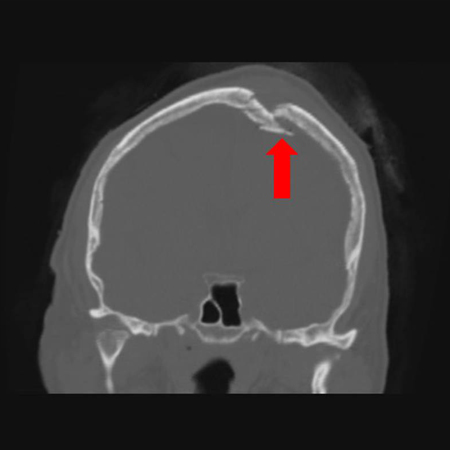

Закрытый перелом головы